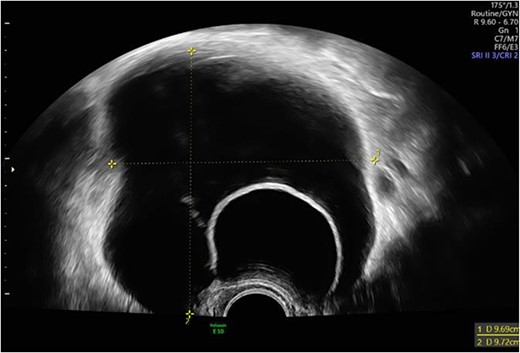

The postoperative course was unremarkable. The postoperative laboratory findings were within the normal range. Before discharge, the kidneys and the urinary bladder were sonographically checked as standard procedure for exclusion of intraoperative ureter injury. In the area of the urinary bladder on the left, an intravesical 51 × 43 mm2 cystic, smooth bounded mass without suspicious perfusion was detected (Fig. 4). This probably corresponded to the finding described preoperatively as an ovarian cyst. The right kidney showed no evidence of congestion, while on the left side a second-degree urinary retention was diagnosed. Therefore, the patient was consulted by a urologist. Sonographically, a double kidney on the left side with a cyst at the upper pole of the upper part and an accentuated calyx system could be diagnosed.

Intravesical cystic mass in the area of the urinary bladder on the left.